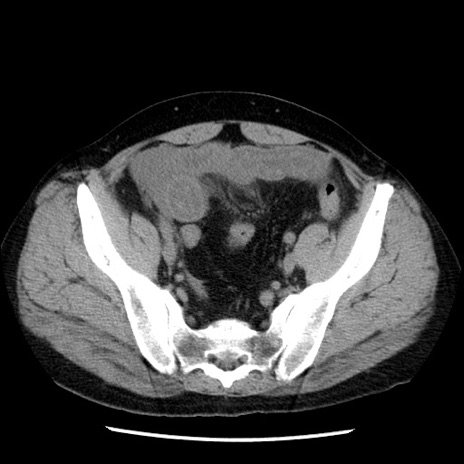

冠状断像

【症例】40歳代男性

【現病歴】2日前から胃痛あり。徐々に周期的な激痛に変化した。本日になっても激痛があるため受診。

【身体所見】意識清明、BT 38-39℃台あり、腹部:膨満、やや硬、右下腹部に圧痛あり。

【データ】WBC 8500、CRP 23.26